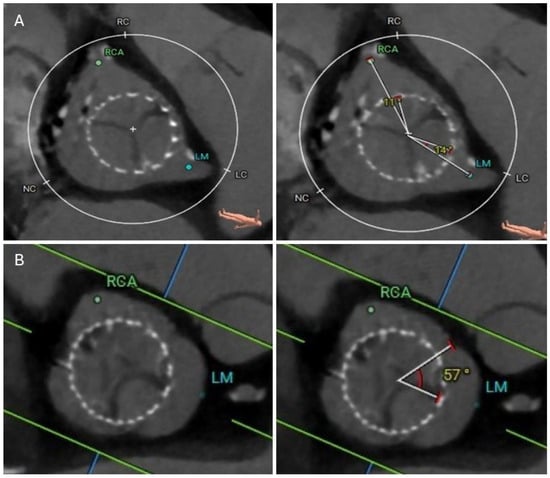

4.4. Coronary Risk Plane (CRP)

4.5. Leaflet Overhang